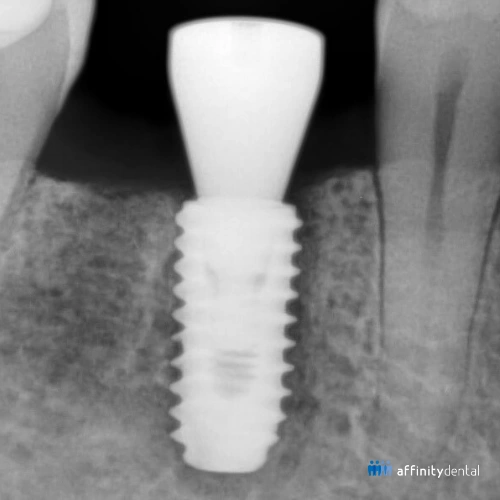

When people think of dental implants, they often picture the visible crown that looks like a tooth. But the real magic happens underneath the gums, inside the bone.

This process is called osseointegration. In simple terms, it is when your natural bone grows around a titanium implant and locks it in place—just like how bone supports your natural teeth.

Think of a dental implant as a screw placed into the jawbone. On its own, it would remain loose and unstable. But with osseointegration, the bone and implant fuse together, making the implant a permanent part of your mouth.